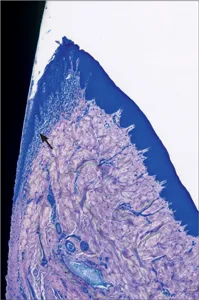

Fig 5 Higher magnification. Intact periodontal ligament connecting the root cementum with the alveolar bone. The collagen fibers invest in both root cementum and alveolar bone.

The fibroblasts of the periodontal ligament synthesize, structure, and remodel the extracellular matrix, which consists of collagen fibers and an amorphous ground substance composed of non-collagenous proteins. Due to its structural configuration, the periodontal ligament provides a flexible attachment of the tooth to the surrounding bone via Sharpey’s fibers into the mineralized tissues (Nanci and Bosshardt 2006).